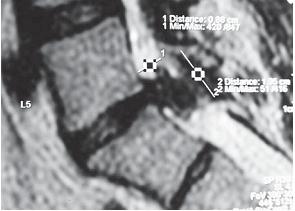

На серии снимков МРТ № 24 наблюдаются дорсальные грыжи межпозвонковых дисков в поясничном отделе позвоночника в сегментах Lv—SI Это самый уязвимый межпозвонковый диск, так как в силу своего анатомического расположения на него приходятся самые большие нагрузки. Как говорится, по счёту «последний», а по уязвимости, первый. Поэтому в нём чаще, чем в других межпозвонковых дисках, возникают, различные осложнения, в том числе и грыжи МРТ № 25